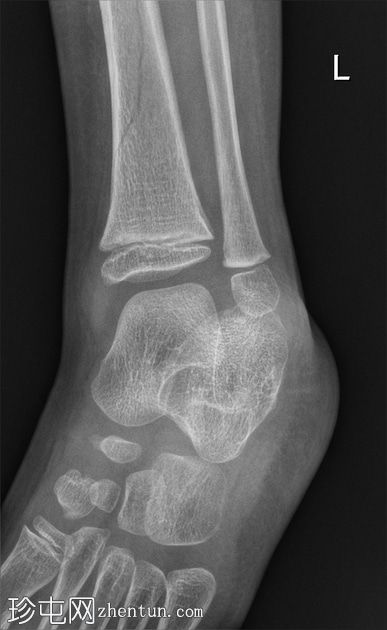

左腿及踝关节

X线片

侧位

斜位

胫骨远端骨干可见一条螺旋状透亮线,提示骨折(正位、侧位)。

应用锐化算法并放大正位片(骨折由近端向远端)和侧位片。

幼儿骨折是指幼儿因扭转(足部着地时股骨内旋)导致的胫骨中远端轻微移位的螺旋状骨折,这种情况可能发生在儿童绊倒时。患者接受了6周的石膏外固定治疗。

请注意,应用锐化骨算法并放大图像后,骨折及其范围会更加清晰可见。